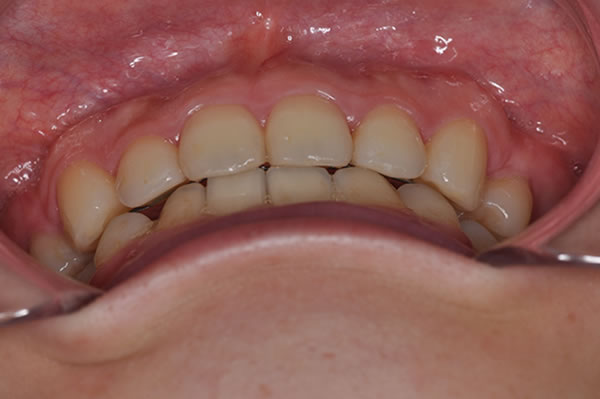

上顎前突症(出っ歯)の矯正症例 ケース01

| 治療前(初診) | 治療後 | |